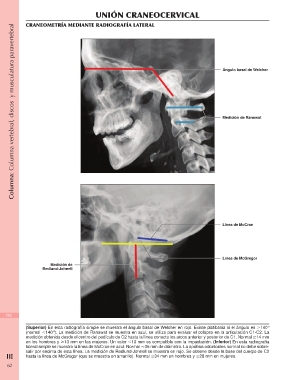

CRANEOMETRÍA MEDIANTE RADIOGRAFÍA LATERAL

Ángulo basal de Welcher

Medición de Ranawat

Línea de McCrae

Línea de McGregor

Medición de

Redlund-Johnell

(Superior) En esta radiografía simple se muestra el ángulo basal de Welcher en rojo. Existe platibasia si el ángulo es Ͼ140°

(normal Ͻ140°). La medición de Ranawat se muestra en azul, se utiliza para evaluar el colapso en la articulación C1-C2. La

medición obtenida desde el centro del pedículo de C2 hasta la línea conecta los arcos anterior y posterior de C1. Normal Ն14 mm

en los hombres y Ն13 mm en las mujeres. Un valor Ͻ13 mm es compatible con la impactación. (Inferior) En esta radiografía

lateral simple se muestra la línea de McCrae en azul. Normal Ϸ35 mm de diámetro. La apófisis odontoides normal no debe sobre-

III salir por encima de esta línea. La medición de Redlund-Johnell se muestra en rojo. Se obtiene desde la base del cuerpo de C2

hasta la línea de McGregor (que se muestra en amarillo). Normal Ն34 mm en hombres y Ն28 mm en mujeres.